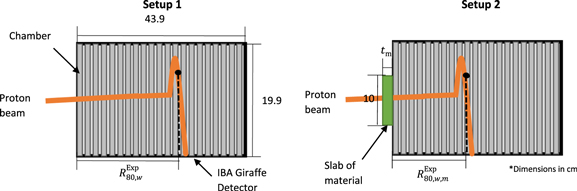

At both energies, a reference PDD was initially taken without an additional material (figure 1, setup 1). Then each slab of material was placed in front of the entrance window of the detector, and the PDD measurement repeated for each material (figure 1, setup 2). PDD measurements were performed to determine the water equivalent thickness  and RSP of the materials (

Figure 1. Experimental setup for water-equivalent thickness measurements (without - setup 1, left - and with - setup 2, right – phantom material in front of the Giraffe detector). The number of ionization chambers shown within detector is reduced to simplify the schematic.